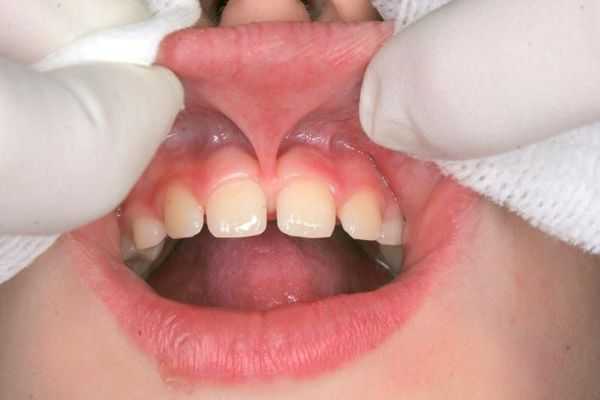

Диастема – видимый межзубный промежуток, разделяющий центральные резцы верхнего (реже – нижнего) зубного ряда. Диастема не только представляет собой эстетический недостаток, но также способствует нарушению речи, возникновению коммуникативных и психологических трудностей. Уточнение причин и сопутствующих диастеме аномалий проводится с помощью стоматологического осмотра, внутриротовой рентгенографии, ортопантомографии, изучения диагностических моделей челюстей. Лечение диастемы может осуществляться терапевтическими (эстетическая реставрация), ортопедическими (коронки, виниры), хирургическими (пластика уздечки верхней губы или языка), ортодонтическими (вестибулярные пластинки, брекеты) методами.

Расстояние между зубами при диастеме составляет от 2 до 6 мм, но иногда может достигать 1 см. Чаще всего промежутки появляются между передними резцами верхней челюсти. На нижней челюсти диастемы встречаются крайне редко [2] .

- Увеличенные или неправильно прикреплённые уздечки губ. Когда уздечка верхней губы крепится слишком близко к краю десны , центральные зубы смещаются и пространство между резцами увеличивается. На нижней челюсти диастемы обычно развиваются из-за утолщённой нижней губы, неправильной формы уздечки или её высокого крепления.

Промежуток между передними резцами образуется при формировании зубной дуги и, как правило, является наследственным признаком. Также на механизм развития промежутков напрямую влияет увеличенный размер уздечки верхней губы. При этом волокна уздечки переплетаются с вершиной межрезцового сосочка и костной перегородкой между зубами.

Большой размер или неправильное крепление уздечек губ. Это — причина 80-90% случаев диастем. Если уздечка верхней губы закреплена слишком низко, это смещает центральные резцы, увеличивает расстояние между ними. Диастема на нижней челюсти может появляться из-за увеличенной толщины уздечки нижней губы, ее слишком высокого прикрепления, неправильной формы или крепления уздечки языка.